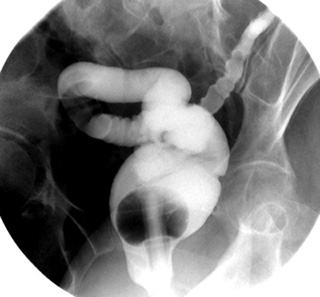

- Roll the patient backward into a RPO position.

- Again instruct the assistant to partially unclamp the tubing

and allow the barium to slowly flow by gravity through the rectosigmoid

colon while you pan back and forth with the fluoroscope between the head

of the barium column and the sigmoid region.

- When the sigmoid colon is well

filled, take a spot image of the rectosigmoid colon in the RPO

position.